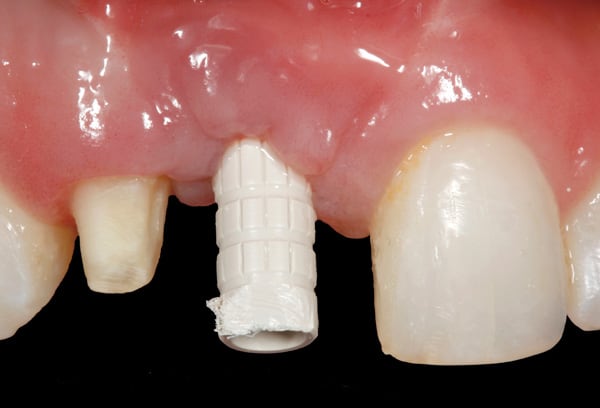

After 6 months of healing of the implant, stage 2 uncovering was performed and the mucosal tissues were allowed to mature for another 2 to 3 weeks. A temporary screw-retained implant cylinder (PreFormance® Temporary Cylinder, Biomet 3i) was joined to the implant and acrylic (Super-T, American Consolidated Mfg, www.pattersondental.com) crown (Figure 8). The subgingival shape of the temporary was modified with additional acrylic and the technique of non-surgical tissue sculpting, which was developed to provide the proper emergence profile to the mucosal tissues.27 It is important that the temporary blanching (ischemia) of the mucosal tissues dissipate after 10 minutes (Figure 9). After 3 weeks, soft-tissue scalloping through gingivectomy was done to recreate the proper shape (ie, gingival zenith)28 and proportion for the mucosal tissues (Figure 10). Fiberotomy on the distal aspect of tooth No. 7 was not performed during treatment; therefore, this papilla was slightly more incisal (longer) than the adjacent papillae (Figure 11). A final impression was made of crown No. 7 and implant No. 8 at the implant level to enable a working cast to be made in the laboratory. An all-ceramic custom abutment was made for implant No. 8 (BellaTek® Encode, Biomet 3i), and splinted full-coverage units were made for crowns No. 7 and No. 829 (Figure 12). The custom abutment was seated intraorally and torqued according to the manufacturer’s recommendation. The crowns were luted with provisional cement (Tempbond® NE, Kerr Dental, www.kerrdental.com) and maintained at 4-month recall intervals (Figure 13). Note the health of the periodontal tissues and their integration with the adjacent teeth and surrounding gingiva, taking a complex esthetic and functional problem for a patient with a high smile line and providing a predictable restorative and esthetic outcome (Figure 14).